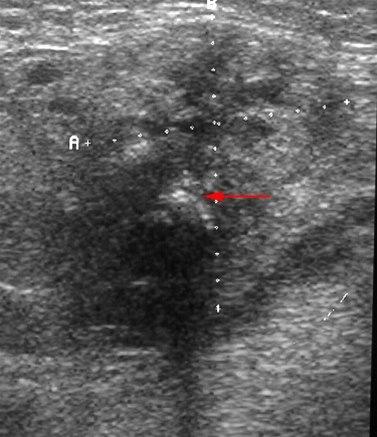

Kroniske betennelsesforandringer i glandula submandibularis med mikroabscesser og en forkalkning (pil) som gir ekkoskygge. Bilde donert av dr. A. Ødegård